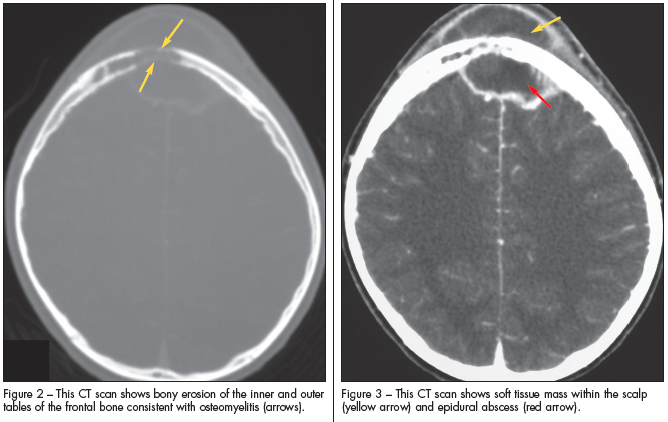

Pott puffy tumor was originally described by Sir Percivall Pott in 1768. In most patients, the process begins with frontal or ethmoid sinusitis (Figure 1) that deteriorates into an associated subgaleal abscess and frontal osteomyelitis (Figure 2). Complications include epidural or subdural abscesses (Figure 3), meningitis, and encephalitis. Periorbital abscesses and cellulitis may also represent complications of worsening sinusitis.

Laboratory studies generally include blood cultures; however, the diagnosis is made radiographically. CT of the head and sinuses is the initial test of choice, because it identifies all the involved structures both intracranially and extracranially. Abscesses are better delineated with contrast scans. MRI may be more useful if cavernous or sagittal sinus thrombosis, orbital involvement, subtle abscesses, or subdural empyema is suspected.